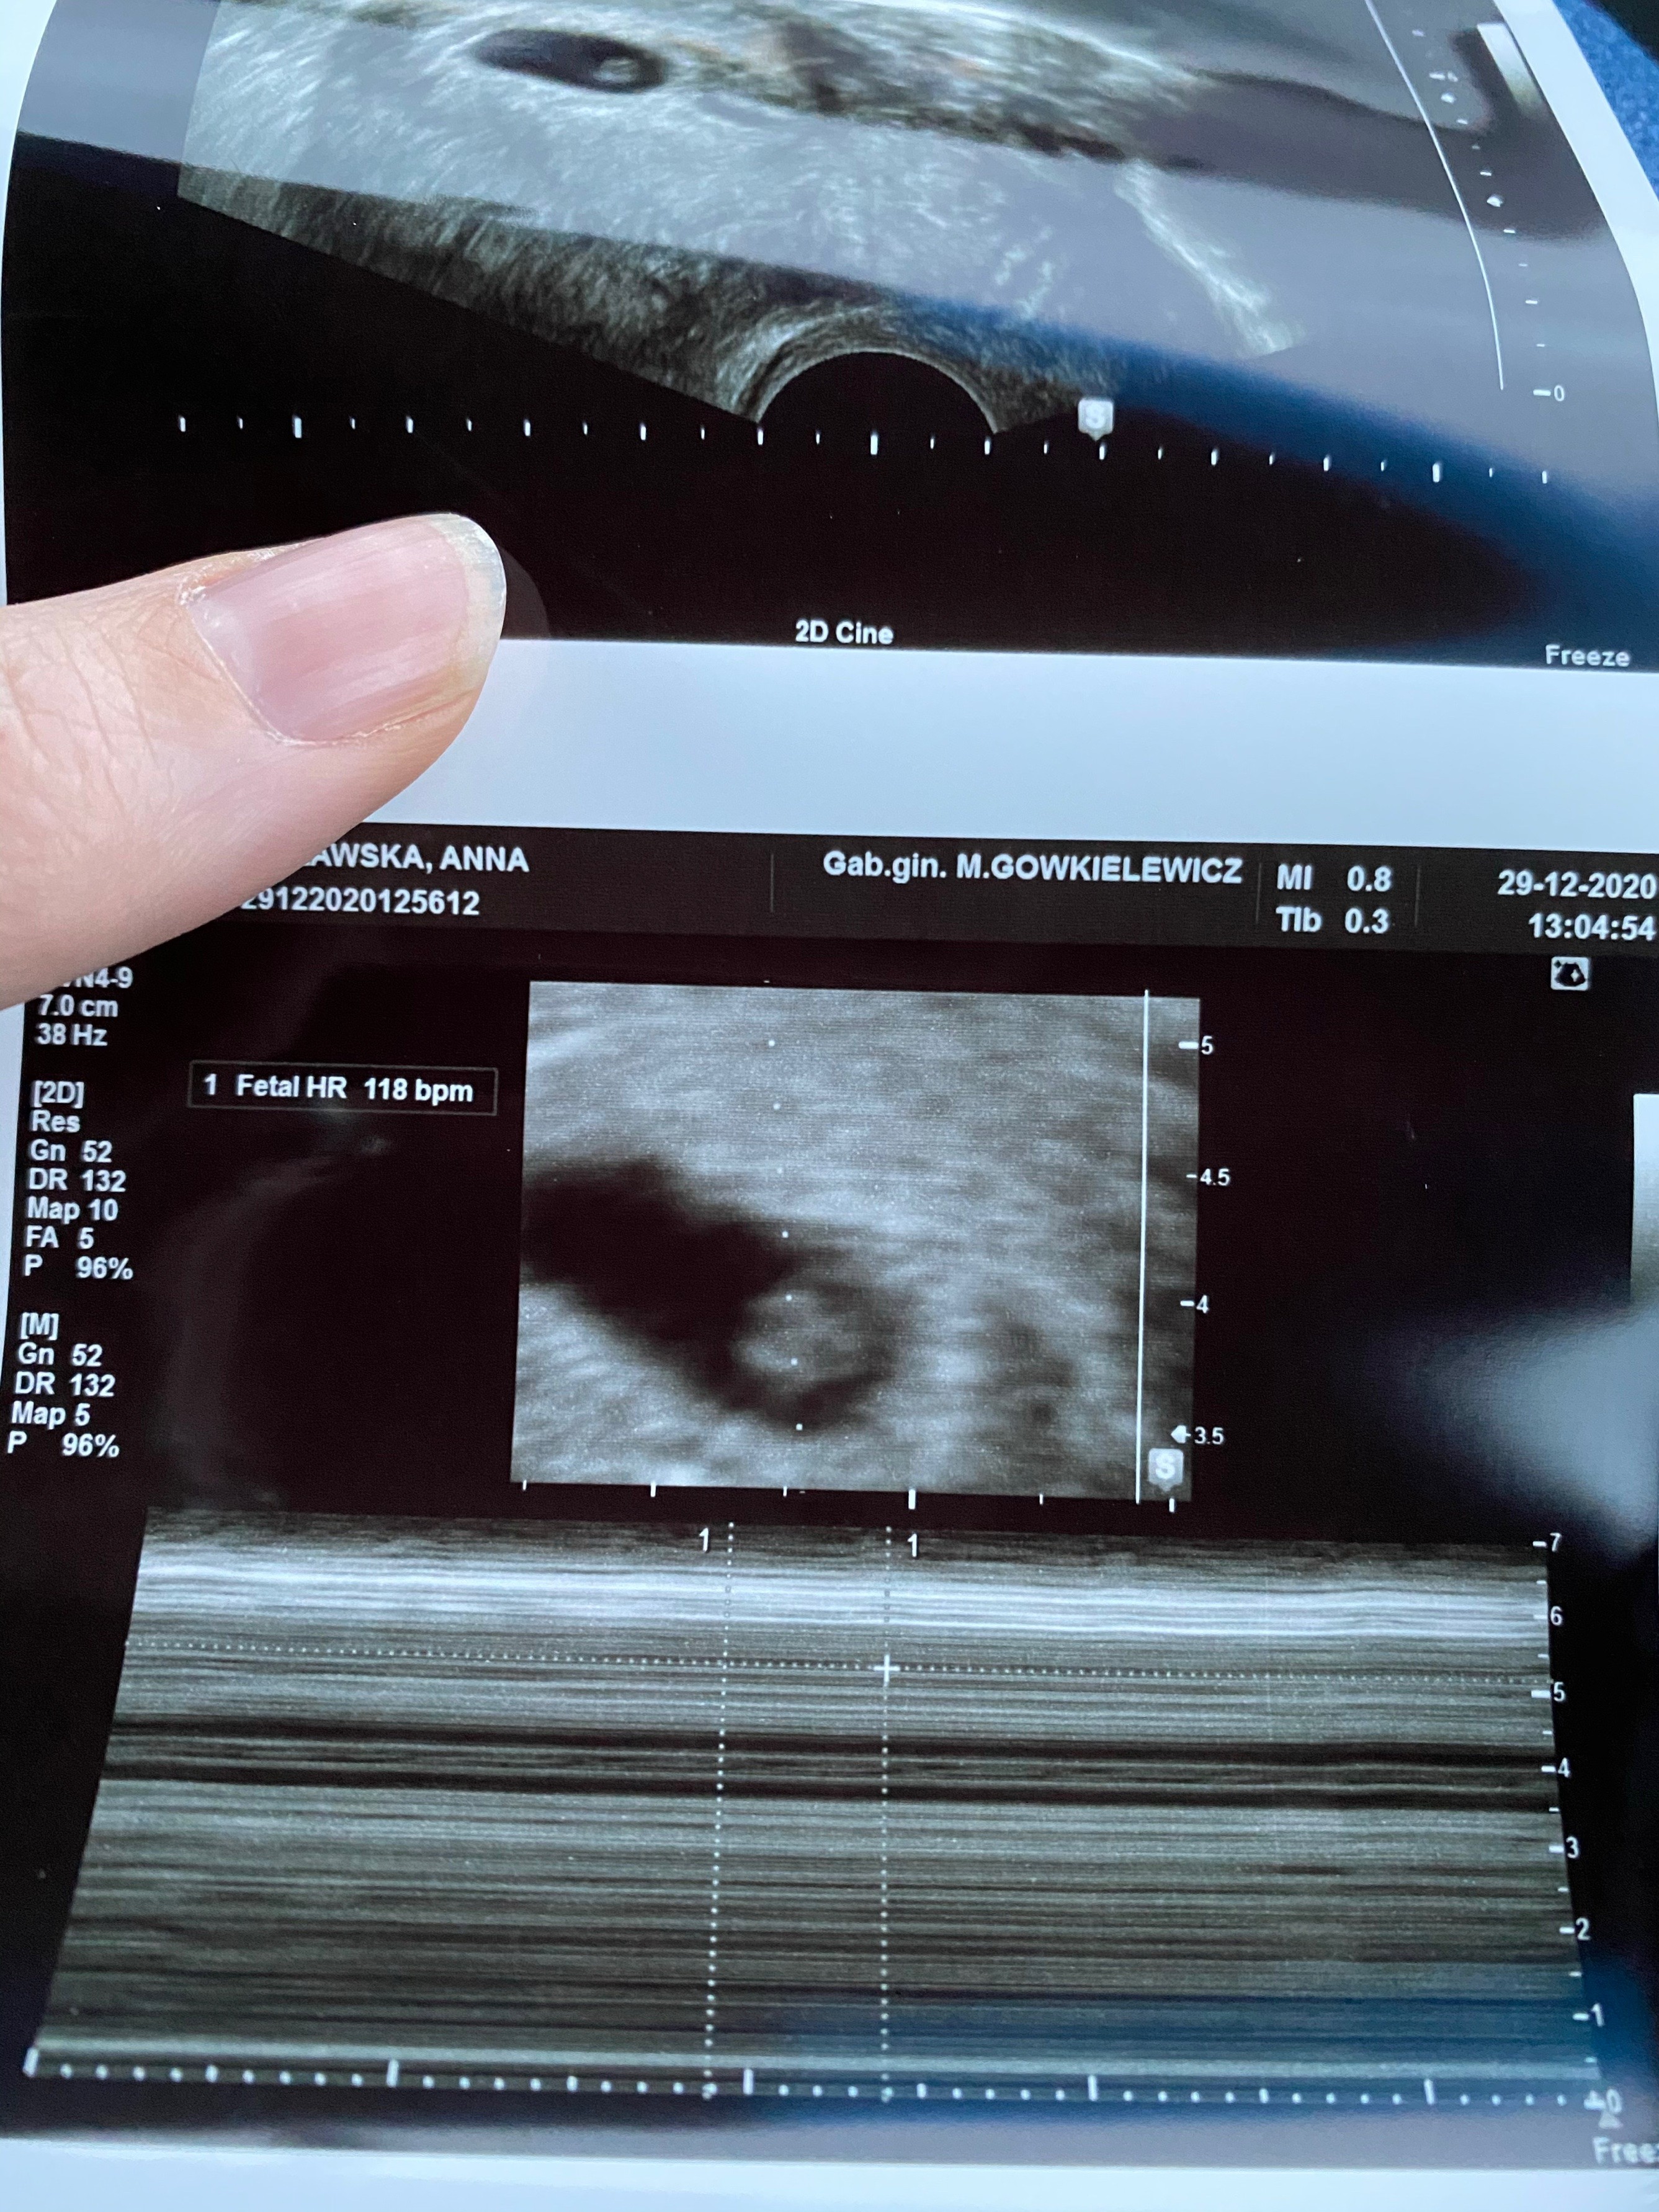

Wszystko dobrze. Maluszek tydzien młodszy ale serduszko pieknie bije. Widzialam jak caly pulsowal.

Termin z usg to 24.08. Odetchnelam z ulga. Zobacz załącznik 1220518